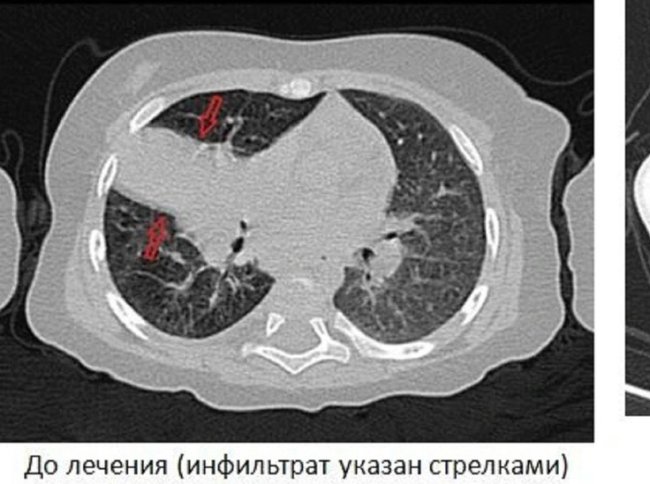

В Ярославской области медикам пришлось лечить трехмесячного младенца от туберкулеза